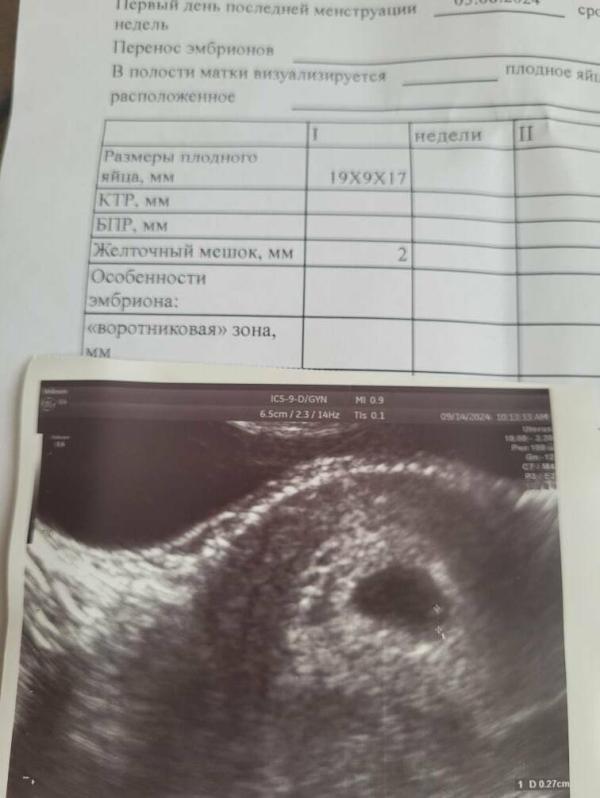

Сходила сегодня на узи и сдала повторный анализ на Хгч с узи что-то совсем не понятно для меня. С трудом увидели желточный мешочек, размеры не понимаю, ощущение что ничего хорошего из этого не выйдет, видимо, я на столько привыкла к плохим результатам, что перестала видеть в чудо. Может есть здесь профи по узи ? Что должно быть по срокам

Плодное яйцо таких размеров может соответствовать сроку 5-8 недель. В среднем 6-7 нед. Сделайте узи через неделю, эмбрион должно быть уже видно